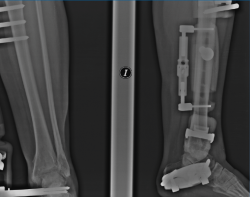

Figura 4. A y B: radiografías anteroposterior y lateral del fijador implantado con la distracción conseguida a nivel articular.

Figura 7. Caso de la Figura 6 con distracción articulada.

Figura 8. Caso de la Figura 6 a los 3 años de la distracción articulada. Obsérvese el mantenimiento del espacio articular a nivel de la articulación del tobillo.